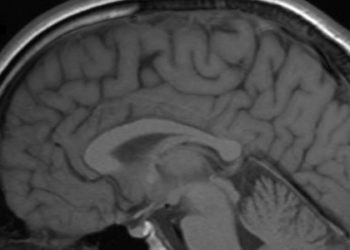

Study Rundown: Premature infants are at increased risk of cerebral palsy, a common childhood motor disorder associated with severe disability. Prenatal magnesium sulfate has become standard to protect fetal brains and lower cerebral palsy risk. However, there is no clear global consensus on when to administer it. The MAGENTA (Magnesium Sulfate at 30 to 34 Weeks’ Gestational Age) trial examined the impact of intravenous magnesium sulfate on pregnant individuals at risk of preterm birth between 30 to 34 weeks of gestation. The results showed no significant difference in death or cerebral palsy rates at 2 years between the magnesium and placebo groups. Interestingly, magnesium reduced respiratory distress syndrome and chronic lung disease in newborns but increased behavioral problems with an unknown biological basis. The study had limitations due to lower-than-expected events, which meant the sample size lacked the power to detect small differences between groups. These findings differ from earlier trials that found beneficial magnesium for reducing risk of cerebral palsy at earlier gestational ages but offer valuable insights for clinical decision-making surrounding the timing and necessity of prenatal magnesium sulfate administration.

In-Depth [randomized clinical trial]: This placebo-controlled randomized clinical trial involved 24 hospitals in Australia and New Zealand from January 2012 to April 2018. A total of 1433 pregnant individuals at risk of preterm birth and 1365 infants were enrolled in the study. Exclusion criteria included those with contraindications to magnesium sulfate (respiratory depression, hypotension, absent patellar reflexes, kidney failure or myasthenia gravis) and those who needed magnesium sulfate for treatment of preeclampsia. Participants were randomized to two groups, either receiving 4 g of magnesium or isotonic normal saline as placebo. The primary outcome was death (stillbirth, death before or after hospital discharge) or cerebral palsy in children at 2 years’ corrected age. At the follow-up, neurological, psychological and caregiver-reported assessments were also completed. There were 36 secondary outcomes that further assessed the health of the pregnant individual and infant. At 2 years, death or cerebral palsy was not statistically significant between groups, with an adjusted risk ratio of 1.19, p=0.57. Adverse events were 3.76 times more likely to occur in individuals who received magnesium versus placebo, but they tended to be minor infusion-related side effects and not life-threatening ones. Overall, the study conducted a thorough assessment of multiple health outcomes postnatally and contributed to the efficacy and safety profile of magnesium sulfate prenatally.